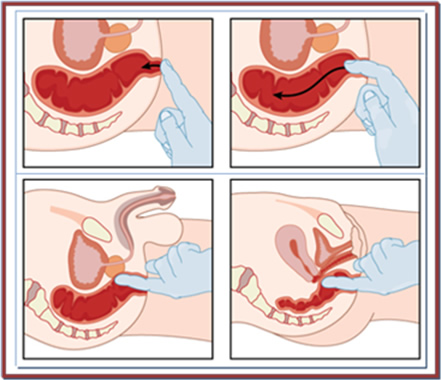

Μακροσκοπικά, διακρίνονται σε έμμισχους και άμισχους (Εικόνα 1).

Εικόνα 1.

Α. Έμμισχος σωληνολαχνωτός αδενωματώδης πολύποδας που αφαιρέθηκε χειρουργικά.

Β. Ευμεγέθης άμισχος λαχνωτός αδενωματώδης πολύποδας ορθού που αφαιρέθηκε χειρουργικά διά του ορθού.

(Από το προσωπικό αρχείο του Γ. Θεοδωρόπουλου)

Η ταξινόμηση κατά Haggitt (Εικόνα 4) βασίζεται στο επίπεδο διήθησης:

- Επίπεδο 0: Χωρίς διήθηση, βαρειά δυσπλασία

- Επίπεδο 1: Το καρκίνωμα διηθεί διά της υποβλεννογονίου μυϊκής στιβάδας, αλλά περιορίζεται στην κεφαλή του έμμισχου πολύποδα

- Επίπεδο 2: Το καρκίνωμα διηθεί έως τον αυχένα, το όριο μεταξύ της κεφαλής και του μίσχου του έμμισχου πολύποδα

- Επίπεδο 3: Το καρκίνωμα διηθεί το μίσχο του έμμισχου πολύποδα

- Επίπεδο 4: Το καρκίνωμα διηθεί τον υποβλεννογόνιο χιτώνα του εντέρου κάτω από το μίσχο του έμμισχου πολύποδα. Όλοι οι κακοήθεις άμισχοι αδενωματώδεις πολύποδες είναι επιπέδου 4 κατά Haggitt.

Ο κίνδυνος λεμφαδενικών μεταστάσεων είναι <1% για έμμισχους κακοήθεις πολύποδες με επίπεδο διήθησης κατά Haggitt 1, 2 και 3, ενώ για τα αδενώματα με επίπεδο 4 κατά Haggitt, έμμισχα ή άμισχα, ο κίνδυνος αυτός κυμαίνεται σε 12 έως 25%.

Η ενδοσκοπική πολυπεκτομή αρκεί για τα καοήθη αδενώματα με επίπεδο διήθησης κατά Haggitt 1, 2 και 3, εφόσον το κακόηθες νεόπλασμα δεν είναι κακής διαφοροποίησης και δεν ανευρίσκεται διήθηση των λεμφαγγείων ή των αγγείων του υποβλεννογόνιου χιτώνα.

Εικόνα 4.

Ταξινόμηση κατά Haggitt